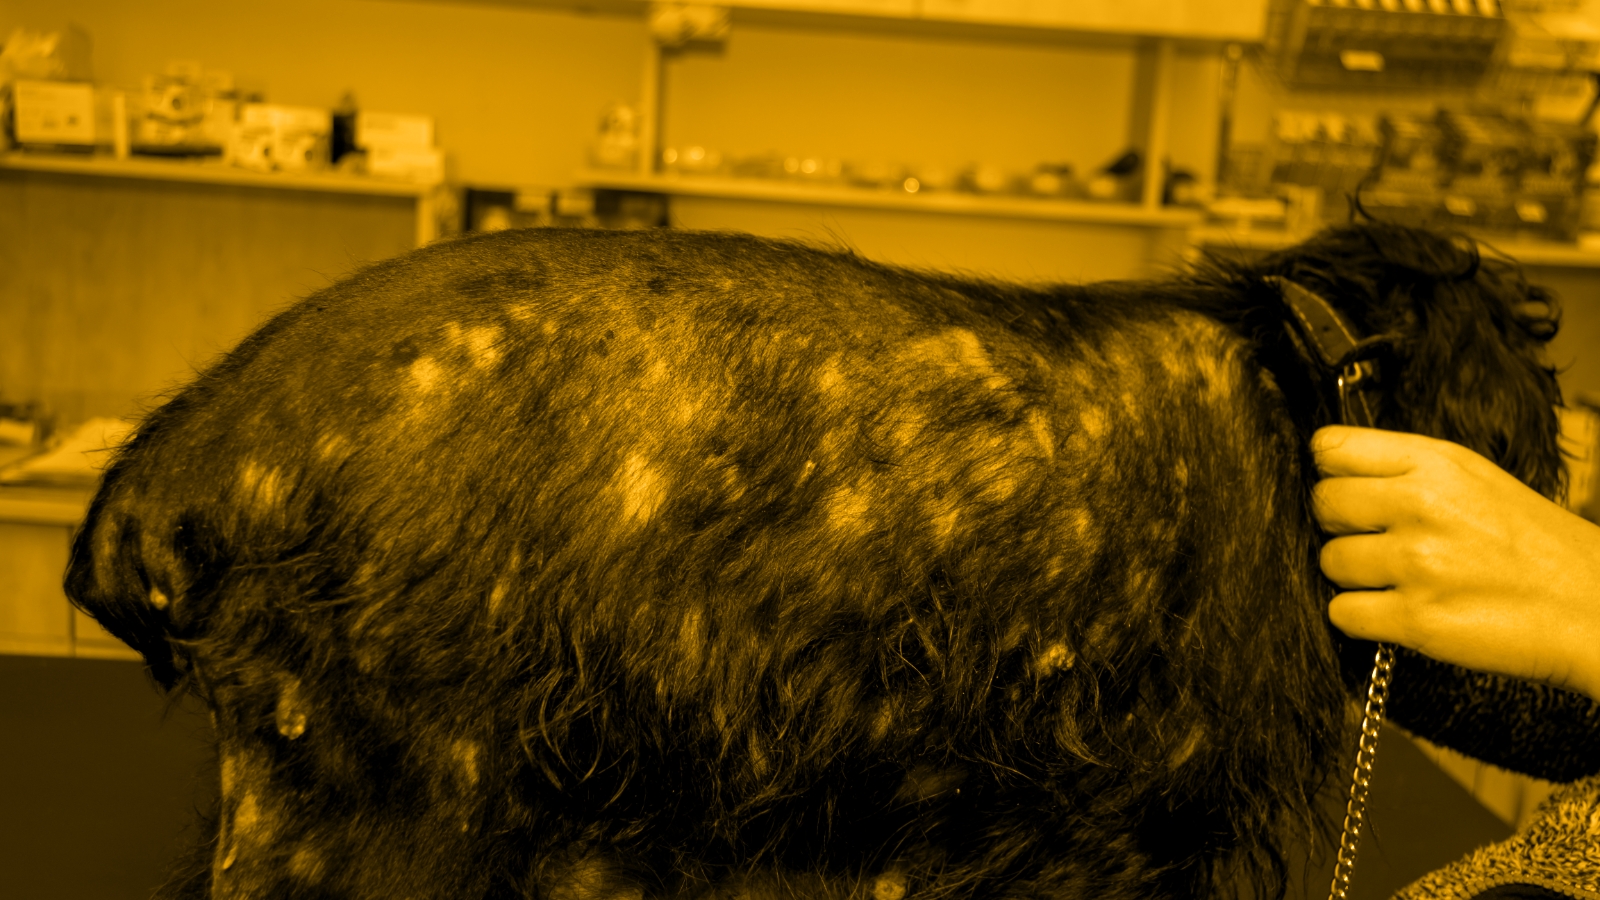

Survey highlights gaps in canine pruritus management expectations

Data from Merck Animal Health show veterinarians and pet owners prioritize fast, effective itch relief for allergic skin disease in dogs.